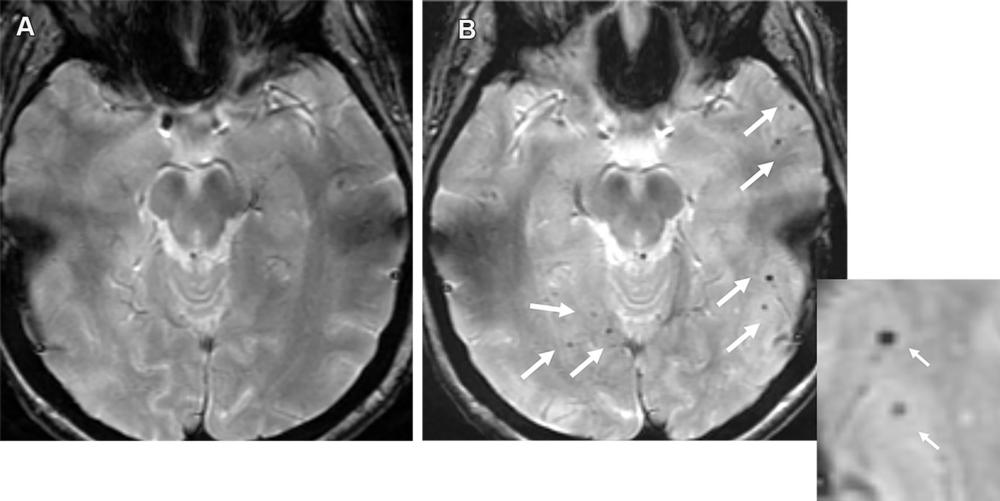

Figure 14. Advanced CAA with inflammatory changes (CAA-RI) in a 76-year-old man. (A, B) Axial susceptibility-weighted images show innumerable microhemorrhages in a peripheral lobar pattern. The patient subsequently presented to the emergency department with mental status changes, and MRI was performed. (C) Axial MR image shows cortical-subcortical edema (arrow) in the left occipital lobe consistent with acute inflammatory changes (CAA-RI). The imaging findings are indistinguishable from those of ARIA, and the differentiation is based primarily on clinical history. Moreover, patients with such a high number of microhemorrhages at pretreatment imaging are usually excluded from MAB clinical trials.

High-res (TIF) version